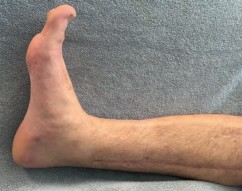

The management of complex tibial shaft fractures with extension into the distal articular surface (the tibial plafond or pilon) represents one of the most formidable challenges in orthopedic traumatology. These injuries typically result from high-energy mechanisms, such as a fall from a significant height or a motor vehicle collision, where axial loading forces are combined with severe rotational and shear vectors. The classic presentation, as highlighted in our index case of a 26-year-old male who fell 3 meters into a hole, involves not only catastrophic bony disruption but also devastating injury to the surrounding soft tissue envelope. The delicate nature of the soft tissues in the distal third of the leg, characterized by sparse muscular coverage and a precarious vascular supply, dictates the entire trajectory of clinical decision-making.

The patho-epidemiology of these injuries is inextricably linked to the incidence of acute compartment syndrome. High-energy axial loads result in rapid swelling, hemorrhage, and edema within the unyielding fascial compartments of the leg. As demonstrated in our reference case, clinical examination often reveals a tense, swollen limb necessitating an immediate four-compartment fasciotomy. The dual-incision technique remains the standard of care to decompress the anterior, lateral, superficial posterior, and deep posterior compartments. The presence of fasciotomy wounds further complicates the surgical approach for definitive internal fixation, requiring strict adherence to the principles of damage control orthopedics (DCO).

In cases involving acute compartment syndrome, the sequelae can be particularly devastating. Even with prompt fasciotomy, some degree of muscle necrosis may occur, leading to late fibrotic contractures, particularly of the deep posterior compartment (resulting in claw toes and equinus contracture). Neurologic deficits, such as foot drop from deep peroneal nerve ischemia, may be permanent, necessitating subsequent tendon transfers or ankle-foot orthoses (AFOs).